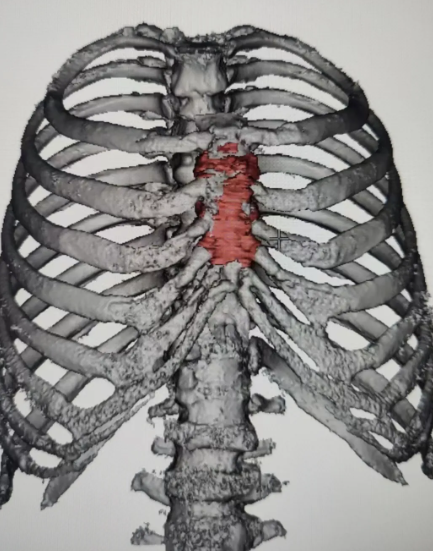

69岁女性患者,因“反复胸疼5月余”入院,查体胸骨区有压痛,入院后完善相关检查,行胸部CT提示:胸骨肿瘤,完善术前检查,行肿瘤切除+胸壁重建术,目前患者已康复出院。

▲胸壁三维重建(橙色区域为胸骨肿瘤)